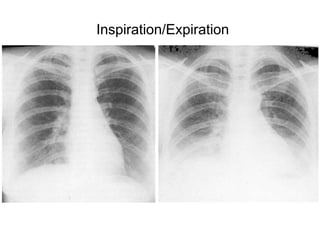

Inspiration/Expiration

• This is useful for determining the size and

shape of the heart, and the state of the

pulmonary blood vessels and lung fields. Most

information is given by a posteroanterior (PA)

projection taken in full inspiration.

• Anteroposterior (AP) projections are

convenient when patient movement is

restricted but result in magnification of the

cardiac shadow.